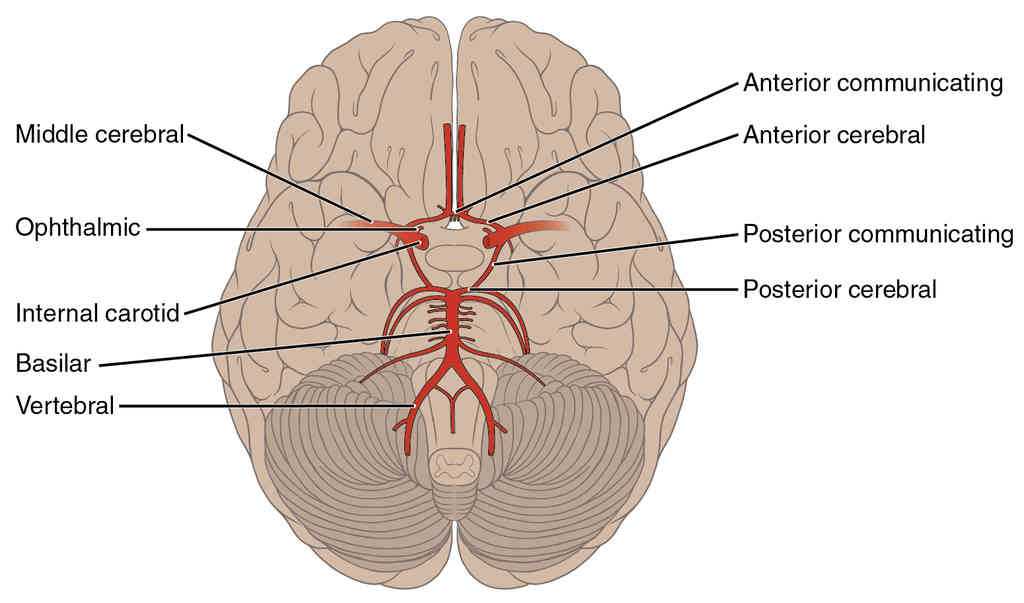

This page is under construction. For now, it is just a resource of the images found in the OpenStax Anatomy and Physiology Handbook. It wil slowly change into a revision tool. Each slide has a number. Use this to refer to the slide. When completed, it will have an unlabelled section, with labelled slides in parallel. On the unlabelled slides, write your answer and use the labelled slide to assess yourself. Keep track by also noting the number on each slide. Improvement at each attempt is important, more so than full marks on a first attempt.